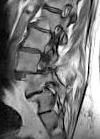

Slipped L4 Disc Image cropped Published May 27, 2017 at 100 × 139 in Tiny Birdwatching and Back Doctor Visit ← Previous Next → Slipped L4 Disc Image cropped Slipped L4 Disc Image cropped Share this: Email a link to a friend (Opens in new window) Email More Share on Pinterest (Opens in new window) Pinterest Like Loading...